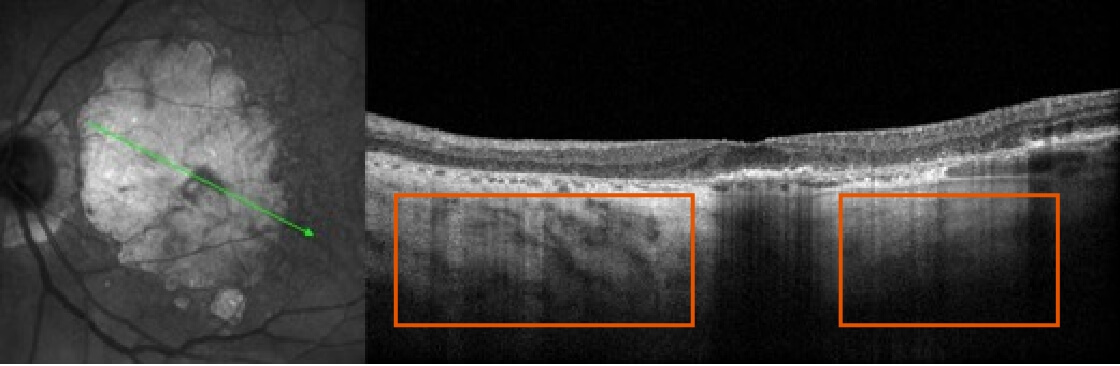

Learn how to recognize GA

OCT=optical coherence tomography.